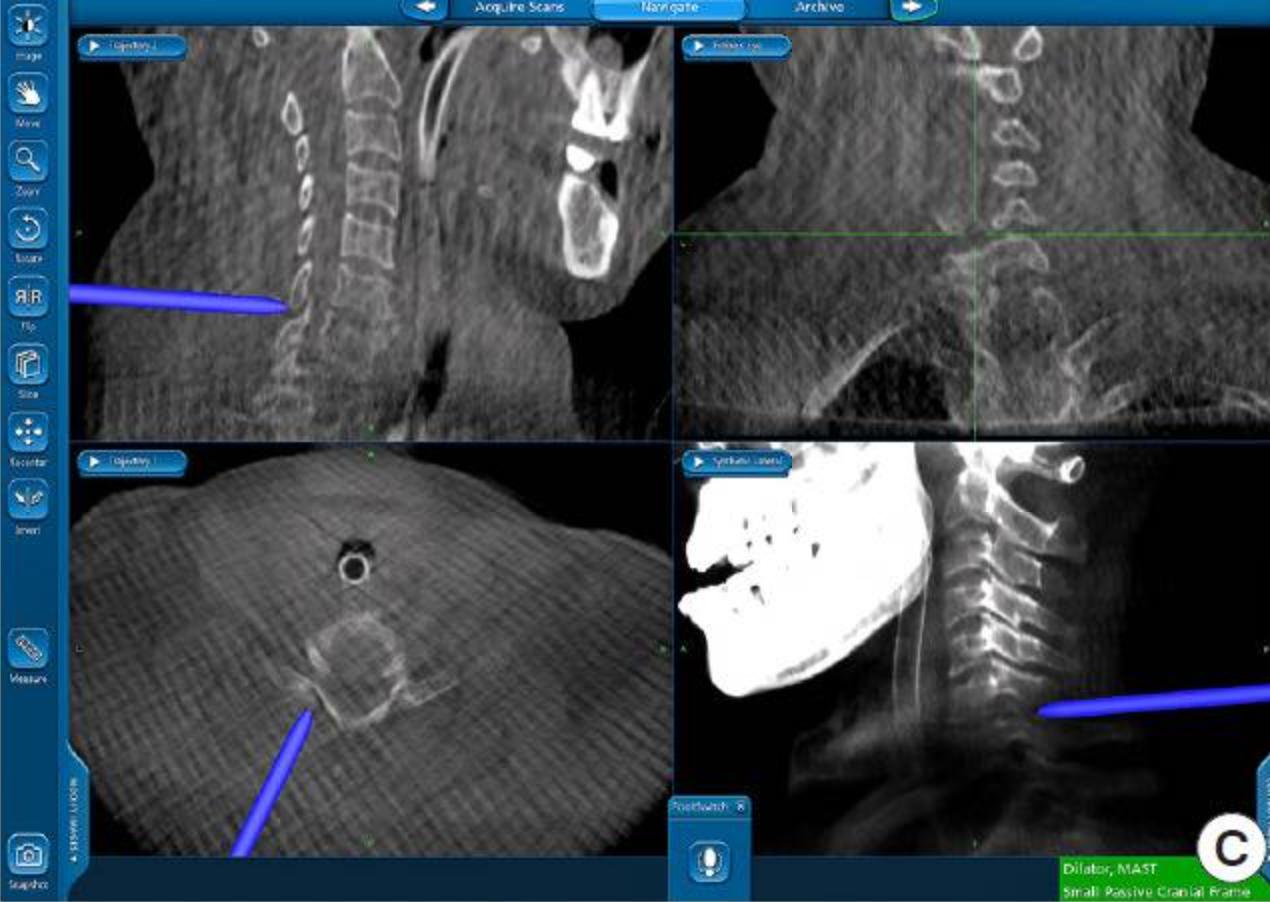

Whatthefutureholds

Spinalnavigationandsurgicalrobotics

Eg A dynamic reference frame fixed on the PSIS and 3D reconstructed images are created using intraoperative CT, connected to navigations A planar probe identifies the best entry point and trajectory Numerous stab incisions can be made or alternatively, a long paramedianincisioncanbeused Oncethenavigatedguideddrillisinplace,acannulaandhighspeeddrillareusedtocreateapathfor instrumentation.

Possibletobeminimallyinvasive,withusing3Dnavigation androboticassistance(usefulincomplexcases,reduces radiationexposureandprovidesimprovedaccuracywith reducedoperationtime)

Roboticassistancecanalsofurtherimproveaccuracy, minimisetheneedforfluroscopyandisfavourableinpatients withunusualanatomicallandmarks